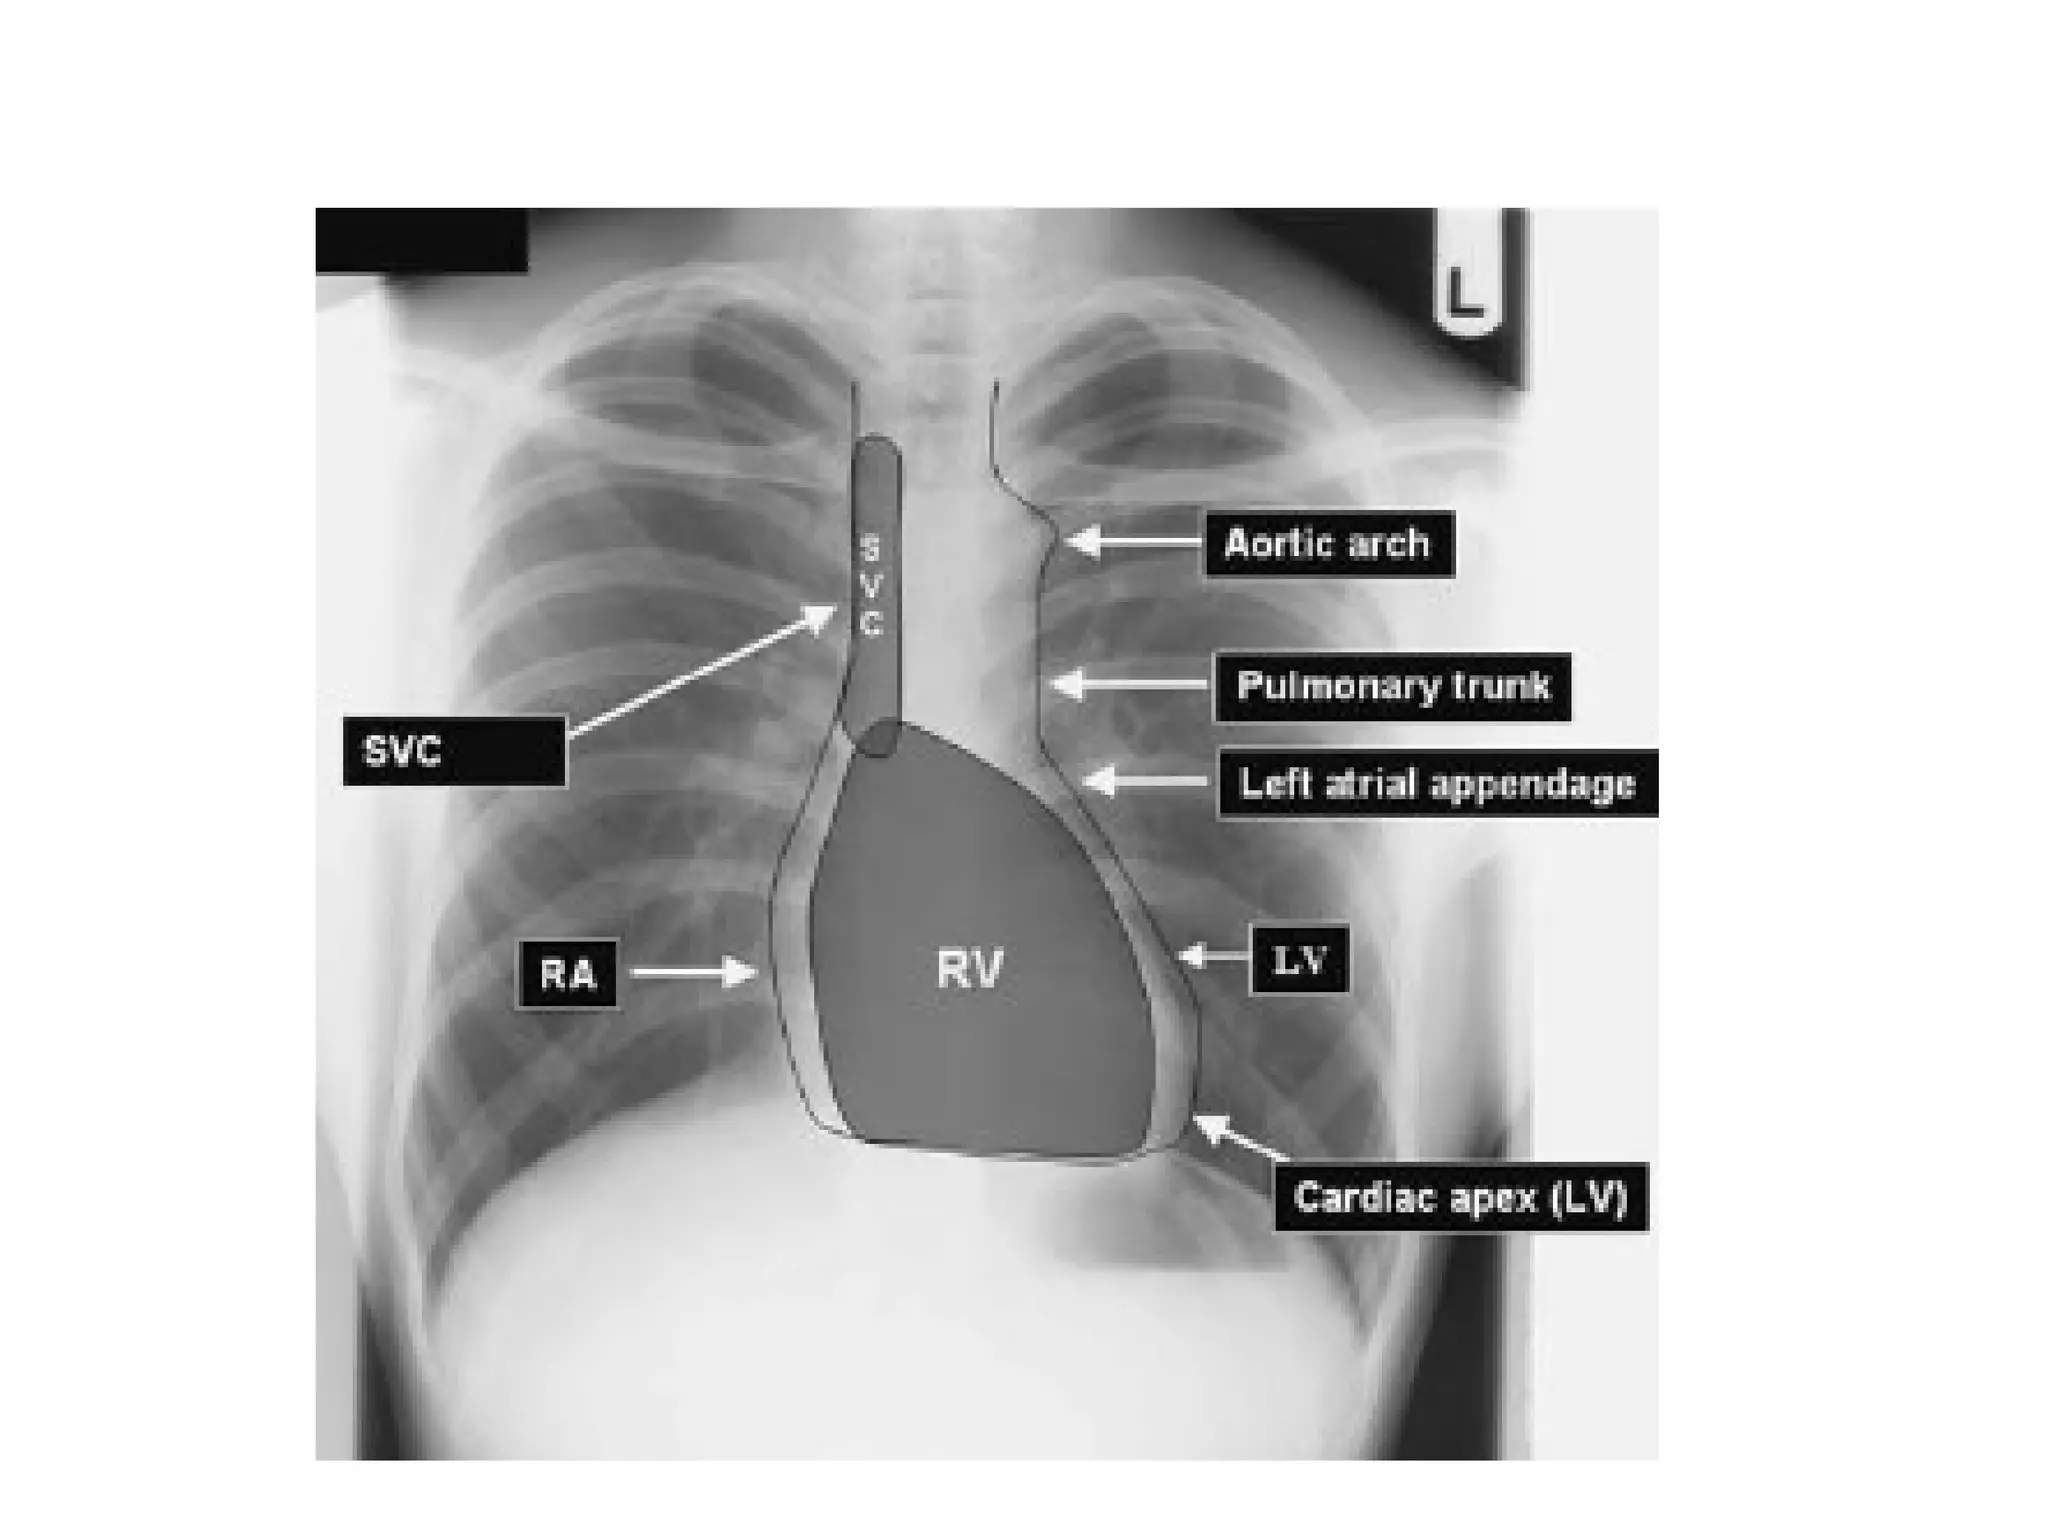

The mediastinum and heart

The central dense shadow seen on PA CXR

comprises the mediastinum, heart, spine and

sternum

The cardiac shadow lies to the left of the midline

and 1/3 to the right although it is quite variable

The transverse cardiac diameter normal for female

< 14.5 cm and for males < 15.5 cm.

The normal cardiothoracic ratio is < 50% on PA

film and < 60% in AP film.

An increase in excess of 1.5 cm in the transverse

diameter on comparable serial films is

significant.

All borders of the heart and mediastinum

should be clearly defined

Superior

Vessels

Vena

Cava          Aortic Arch

Ascending

Aorta        Pulmonary Artery

Right          Left Atrium

Atrium

Inferior        Left Ventricle

Cava

The mediastinum andheart The central dense shadow seen on PA CXR comprises the mediastinum, heart, spine and sternum The cardiac shadow lies to the left of the midline and 1/3 to the right although it is quite variable The transverse cardiac diameter normal for female < 14.5 cm and for males < 15.5 cm. The normal cardiothoracic ratio is < 50% on PA film and < 60% in AP film. An increase in excess of 1.5 cm in the transverse diameter on comparable serial films is significant.

All borders ofthe heart and mediastinum should be clearly defined In babies and young children the normal thymus is a triangular sail shaped structure with well defined borders which may be wavy.

Superior Vessels Vena Cava Aortic Arch Ascending Aorta Pulmonary Artery Right Left Atrium Atrium Inferior Left Ventricle Vena Cava

Aortic Knob/Arch Descending Ascending Aorta Aorta Left Atrium Right Left Ventricle Ventricle Inferior Vena Cava